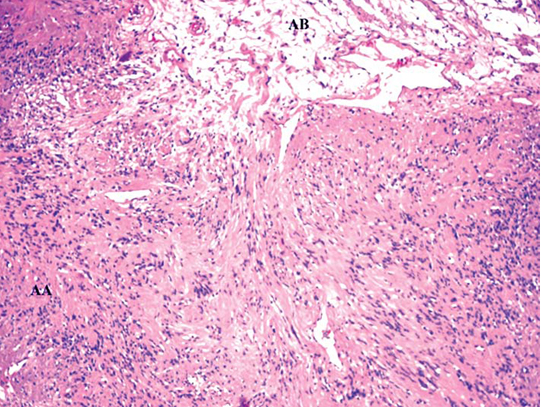

A 60-year-old female presented to the Departement of Orthopaedics with complaints of a painful swelling over the right distal forearm (approximately 8x4x5cm) on the medial aspect [Table/Fig-1,2] which was noticed six years ago which had gradually progressed to present day state. The pain was burning type, non-radiating and was not associated with any motor or sensory deficit. An ultrasonograpghy of the swelling was performed, which suggested the swelling to be arising from the ulnar nerve. She underwent excisional biopsy of the swelling under general anaesthesia. Incision was taken along the length of the swelling; the epineurium was excised and by gentle dissection using an artery forceps; a plane was made between the swelling and the nerve. The swelling was single, solitary, firm, eccentric to the nerve and yellow in colour suggestive of neurogenic origin. The plane was extended all around between the swelling and the nerve, ensuring that at no point the nerve would be damaged. At a point of attachment of the epineurium with the nerve, the epineurium was diretcly cut from the nerve without causing damage to the nerve. The swelling was removed as a single solid mass [Table/Fig-3a&b]. The epineurium was sutured using a non-absorbable sutures and the wound was closed. The swelling was sent for histopathological analysis, which was suggestive of a benign Schwannoma with typical Antoni A and Antoni B areas [Table/Fig-4]. Antoni A areas were composed of spindle shaped schwann cells arranged in interlacing fascicles with nuclear palisading. The Antoni B areas showed loose meshwork of gelatinous tissue. She was relieved of her forearm complaints at follow up.

Histopathological slide of the schwanoma. Showing Antoni A(AA) and Antoni B (AB) cells. (Staining done using Haematoxylin & Eosin stain with a magnification of 200 X).